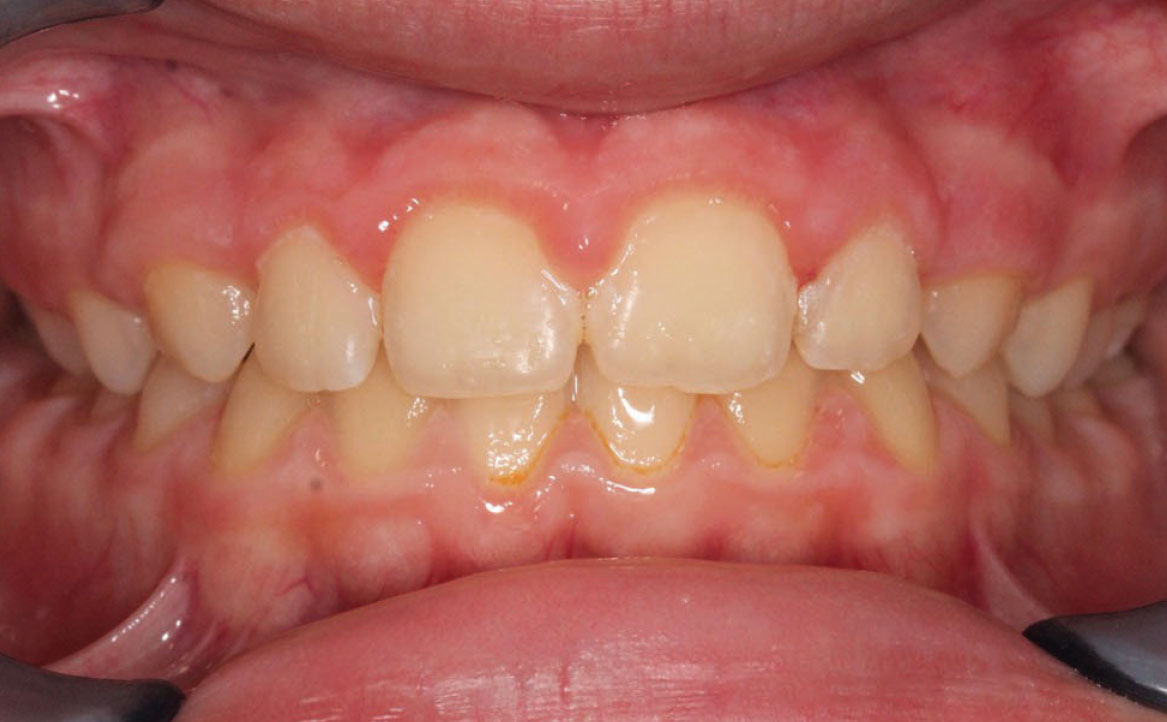

Fig. 4A Foto intraorale in massima intercuspidazione.

A livello intraorale sul piano sagittale è osservabile I classe molare destra e sinistra e classe canina non valutabile per mancanza degli elementi dentari durante la fase di permuta.

L’overjet e l’overbite sono entrambi ridotti in massima intercuspidazione. Trasversalmente il mascellare superiore è contratto (fig. 4-7).